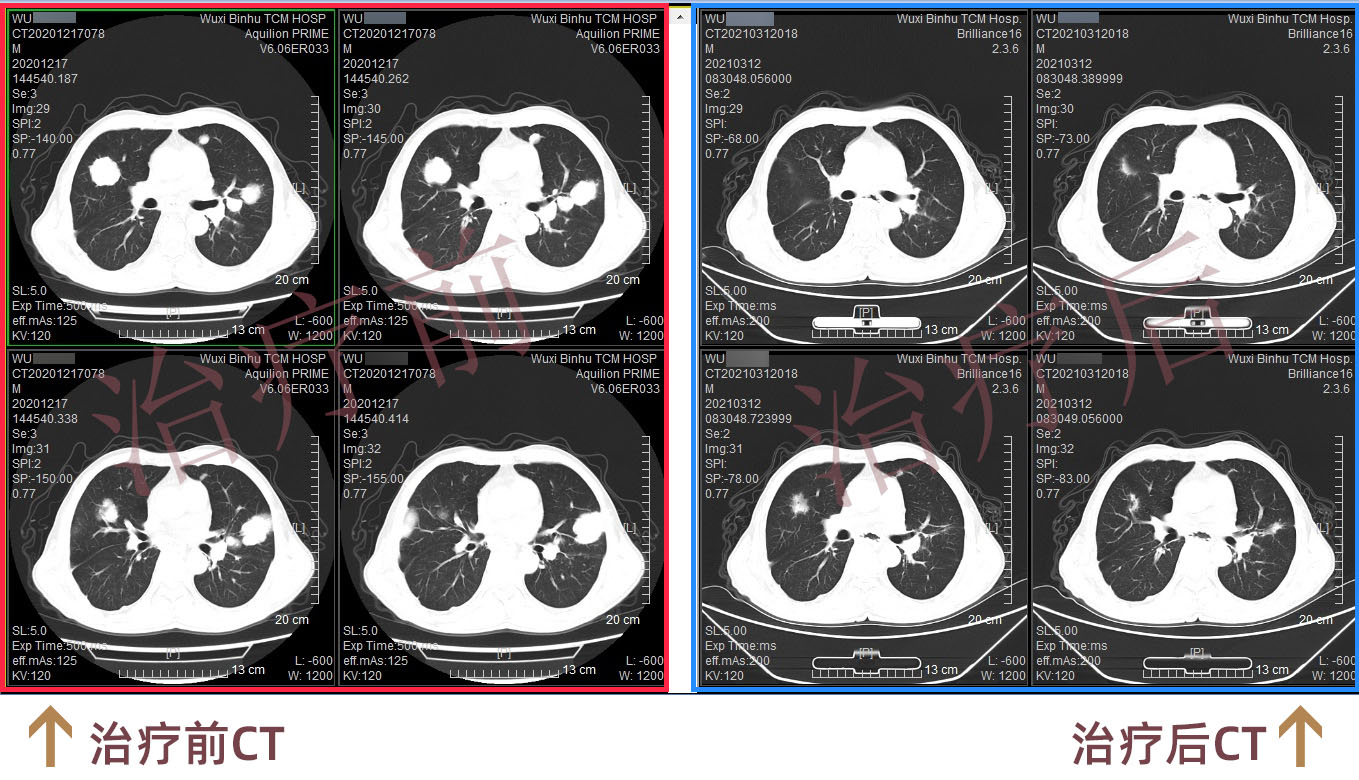

据了解,吴先生1年多前在外院做了胸腔镜中转开放食管拔脱术+空肠造瘘术,术后病理:食管上段中分化鳞状细胞癌,癌组织累及外膜层,脉管内见癌栓,淋巴结见癌转移。术后辅助放化疗期间出现病情进展,两肺、右侧锁骨区及纵隔多发转移,自行口服多种外购靶向药物。定期复查CT提示两肺多发小结节均较前增大(******径约41mm)。

经过两程治疗后,行CT评估患者两肺转移瘤较前明显缩小,进食梗噎及腹胀症状也得到缓解。